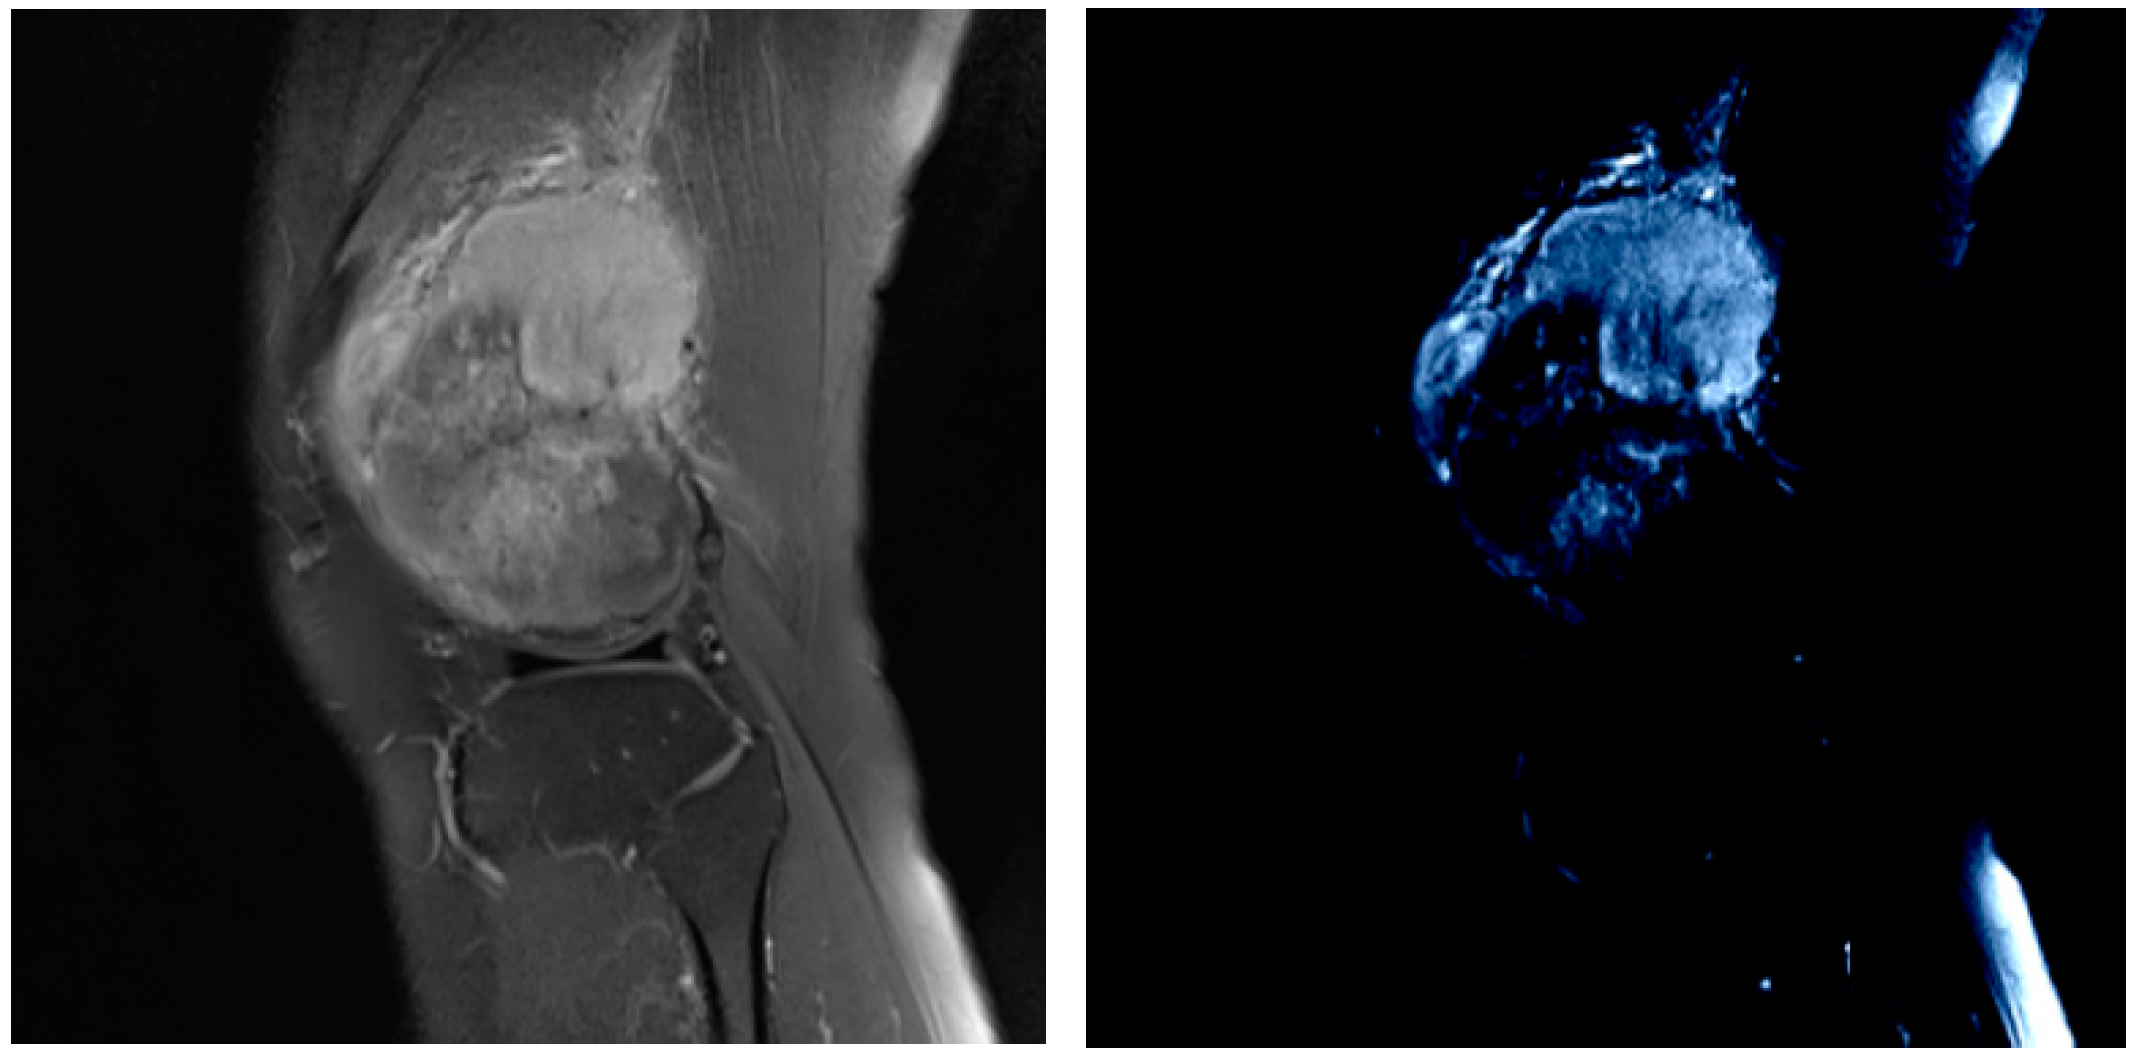

Multi-Scale Tumor Localization Based on Priori Guidance-Based Segmentation Method for Osteosarcoma MRI Images

- This paper proposed a prior-guided-based MRI image segmentation method for osteosarcoma (PESNet), which adds a priori generation and feature enrichment network to effectively improve the localization accuracy and segmentation accuracy of multi-scale tumors.

- The datasets used in this experiment were all from more than 200 real samples from the Second Xiangya Hospital. The results showed that the proposed segmentation method outperforms other methods. The prediction results of the model can be used as an auxiliary basis for doctors’ clinical diagnoses and improve the accuracy of diagnosis.

- Prior Generation. In contrast to the adverse effects of high-level features on the performance of few-shot segmentation, prior segmentation frameworks use these features to provide semantic cues for the final prediction. We performed prior generation processing on MRI images of osteosarcoma to reduce the interference of invalid active segmentation regions on the final prediction, thereby improving the efficiency of image processing.

- Image analysis and segmentation. The segmentation model in this paper is a feature enrichment network based on prior guidance. When training the model, the MRI image of osteosarcoma and its preprocessed mask were input into the network to confirm loss function, and the error segmentation rate of the osteosarcoma image was reduced through repeated training.